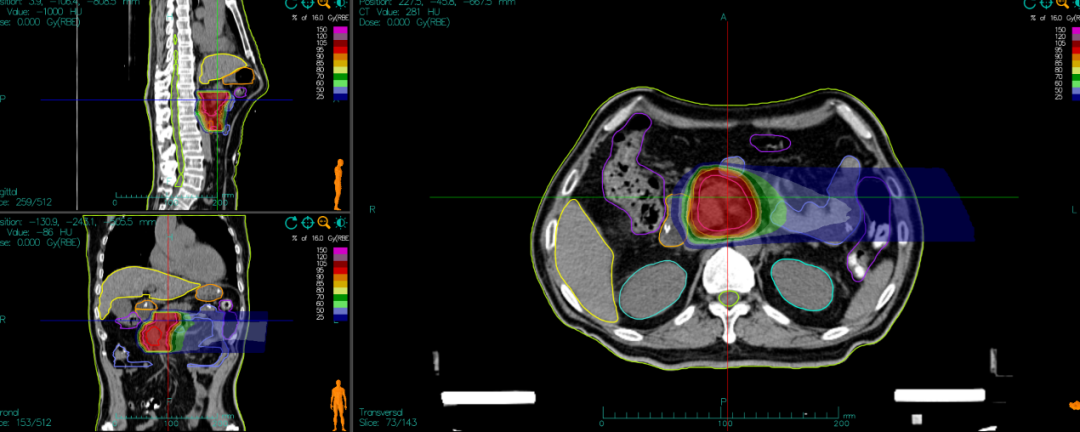

[Carbon Ion Radiotherapy Plan]

- Carbon ion radiotherapy dose:

- PTV 36Gy (RBE)/9 fractions, followed by a reduced-field boost.

- PTV boost 18Gy (RBE)/4 fractions, 4.5Gy (RBE) per fraction.

Carbon ion radiotherapy, as an advanced radiation therapy technology, possesses unique physical and biological properties. It enables precise targeting of tumor tissue while minimizing damage to surrounding normal tissues, offering significant therapeutic advantages for pancreatic cancers in challenging locations that are difficult to resect surgically. However, the application of new technologies is not without hurdles. The treatment team engaged in repeated discussions and research, tailoring a personalized carbon ion radiotherapy plan based on the patient's specific condition, meticulously defining the irradiation field and dosage. Considering the patient's treatment tolerance, four cycles of standard systemic chemotherapy for pancreatic cancer were administered after radiotherapy, ultimately achieving success and allowing the patient to return to a normal life.